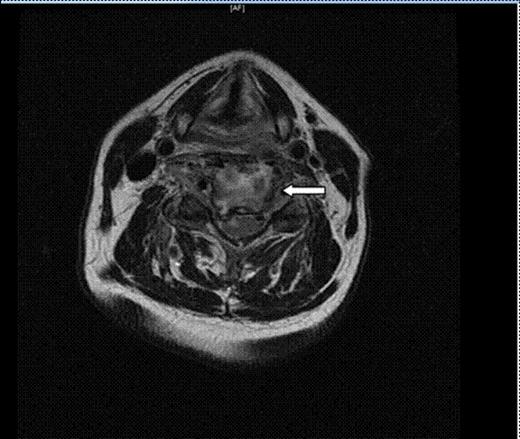

A 68 years old retired tennis coach was urgently admitted under the care of the ENT team following an alarming outpatient MRI scan result. The patient was referred with a six weeks history of progressive difficulty swallowing solids. Initially the patient was seen by his GP due to neck pain after riding his bicycle. It was clinically diagnosed as whiplash and treated successfully with analgesia and physiotherapy for 5 weeks. No history of URTI or trauma was reported. However, progressively the patient developed difficulties swallowing solids and described an uncomfortable “lump in his throat” sensation. The patient was, at all times apyrexial and his ENT examination was unremarkable except for limited extension of his neck and raised inflammatory markers. Due to these clinical findings, an urgent MRI neck scan with contrast was requested showing an extensive retro-pharyngeal enhancing collection associated to an epidural collection extending from C2 to C5/6. This collection indented the cord, particularly on the right. In addition, there was enhancement of the C4 and C5 vertebral bodies consistent with osteomyelitis (Figure 1 & 2).

Axial T2 FSE cervical image. There is enhancement of the C4 and C5 vertebral bodies consistent with osteomyelitis